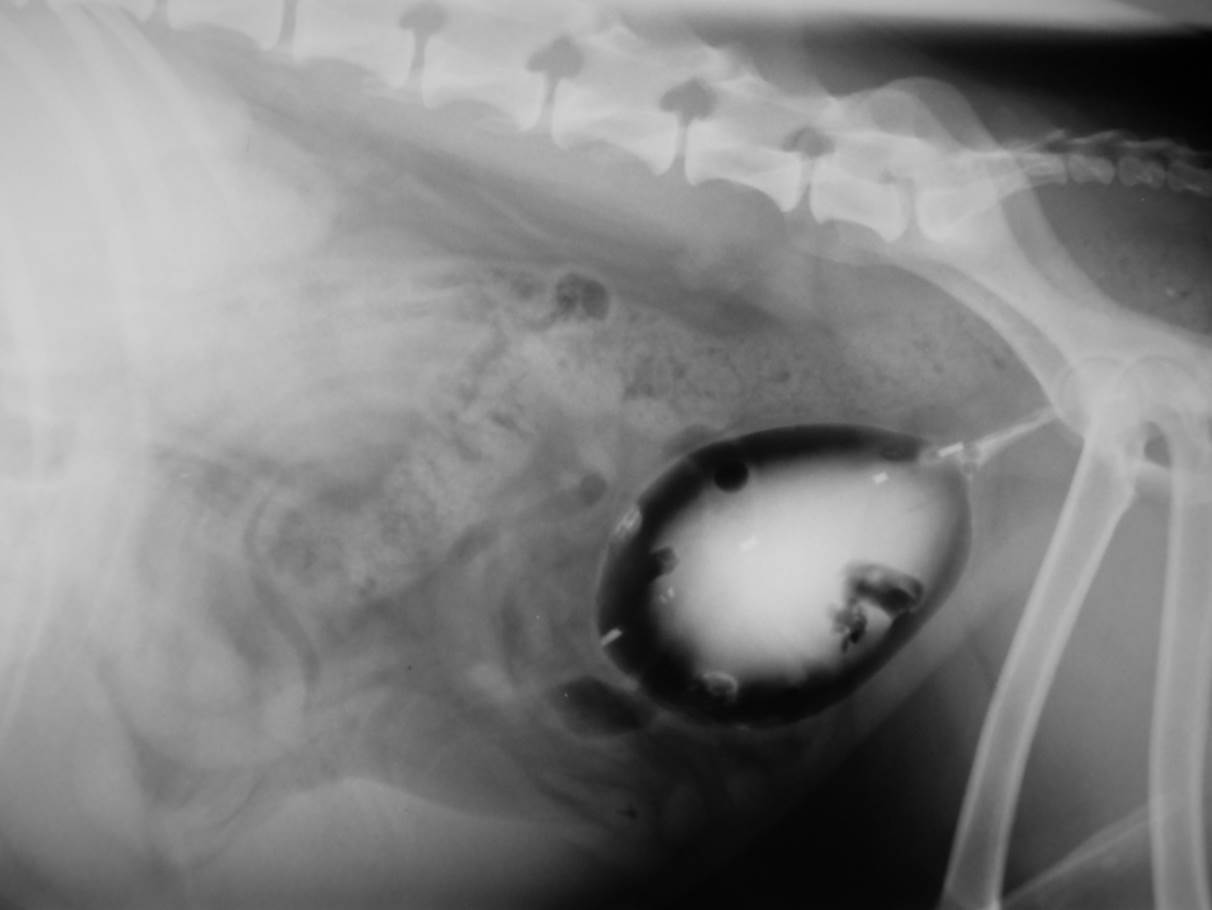

Case Nutty

Discuss this case?

–loss of the normal tear drop shape of the bladder

–urethra relatively short/kinked

–urinalysis including culture

–treatment trial with phenylpropanolamine +/- estriol